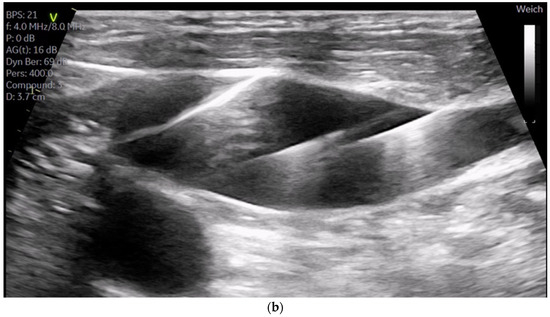

The cannulation of peripheral vessels for the purpose of establishing cardiopulmonary bypass (CPB) in minimal invasive cardiac surgery requires a meticulous approach. This is necessary in order to facilitate optimal redirection of blood flow. The femoral artery and vein, as well as the right internal jugular vein, are commonly employed vessels for cannulation [9]. These vessels offer accessible peripheral entry points for the insertion of cannulas, allowing for the efficient initiation of CPB while minimizing trauma to surrounding tissues [20]. Furthermore, advancements in surgical techniques have enabled the utilization of peripheral vessels such as the axillary artery, providing alternative cannulation sites that further enhance the minimally invasive nature of the procedure. This is achieved by potentially beneficial antegrade flow during cardiac procedures, which is currently under investigation [21]. By carefully selecting and cannulating these vessels, surgeons can effectively establish CPB with precision and safety, thereby facilitating successful outcomes in minimal invasive cardiac surgery. For femoral veins, a lengthy cannula (Bio-Medicus 23/25 FR multistage femoral venous cannula, Medtronic, Minneapolis, MN, USA) is introduced into the inferior vena cava, primarily via the right femoral vein, with echocardiographic guidance (refer to Videos S1 and S2). According to the established protocol, the guidewires are visualized. The venous wire and cannula are depicted through TEE in the midesophageal bicaval view (see Figure 1a,b). The arterial wire is visualized in the descending aortic short-axis (SAX) and long-axis (LAX) views (see Figure 2 and Video S3). The exclusion of malposition such as in the hepatic vein or interatrial septum perforation is carried out.

Figure 2.

Shows the arterial wire in the descending aortic short-axis (SAX) and long-axis (LAX).